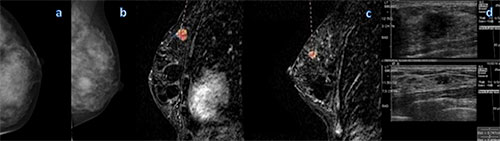

Multi-centric cancer detected at breast MR imaging (MRI) that is occult at mammography appears to represent a larger tumor burden in approximately one-quarter of patients and can upstage the diagnosis, resulting in potential changes in treatment, according to new research published online in Radiology.

Researchers found known index cancers were more likely to be invasive than MRI-detected multi-centric cancers (88 percent vs. 76 percent, P = .023). Ductal carcinoma in situ (21 of 87 lesions [24 percent]; 95 percent CI: 15, 36) represented a minority of additional MRI–detected multi-centric cancers. Overall, the size of MRI-detected multicentric invasive cancers (median, 0.6 cm; range, 0.1-6.3 cm) was smaller than that of the index cancer (median, 1.2 cm; range, 0.05–7.0 cm; P = .023), although 17 of 73 (23 percent) (95 percent CI: 14, 35) patients had larger MRI–detected multi-centric cancers than the known index lesion, and 18 of 73 (25 percent) (95 percent CI: 15, 36) had MRI–detected multi-centric cancers larger than 1 cm.

MRI–detected multi-centric cancers and index cancers differed in histologic characteristics, invasiveness, and grade in 27 of 73 (37 percent) patients (95 percent CI: 26, 49). In four of 73 (5 percent) patients (95 percent CI: 2, 13), MRI–detected multi-centric cancers were potentially more biologically relevant because of the presence of unsuspected invasion or a higher grade.